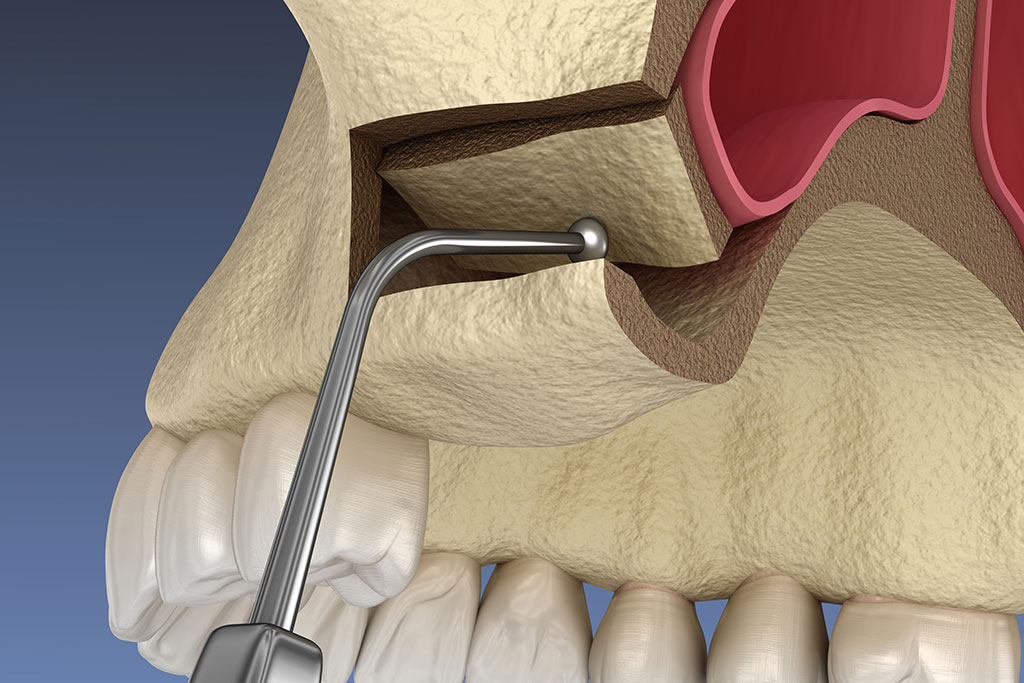

Az arcüreg emelés (sinus lift) egy speciális szájsebészeti beavatkozás, amely során lehetővé tesszük a felső állcsont csontmennyiségének a növelését, hogy megfelelő állapotot biztosítsunk a fogászati implantátumok számára. Az eljárást akkor végezzük, ha az implantátum behelyezéséhez nincs elegendő csontmagasság a felső állcsontban, az őrlőfogak és a kisőrlők területén. Ez gyakran előfordul, amikor a fogak eltávolítását követően a felső állcsont sorvadásnak indul, emiatt anatómiailag az arcüreg is lejjebb kerül, elvékonyodik a csont. Az eljárás során az arcüreget (sinus) bélelő nyálkahártyát emeljük fel, ami alá csontpótló anyagot helyezünk be, biztosítva a természetes csont képződését az adott területen.

A sinus lift típusai: